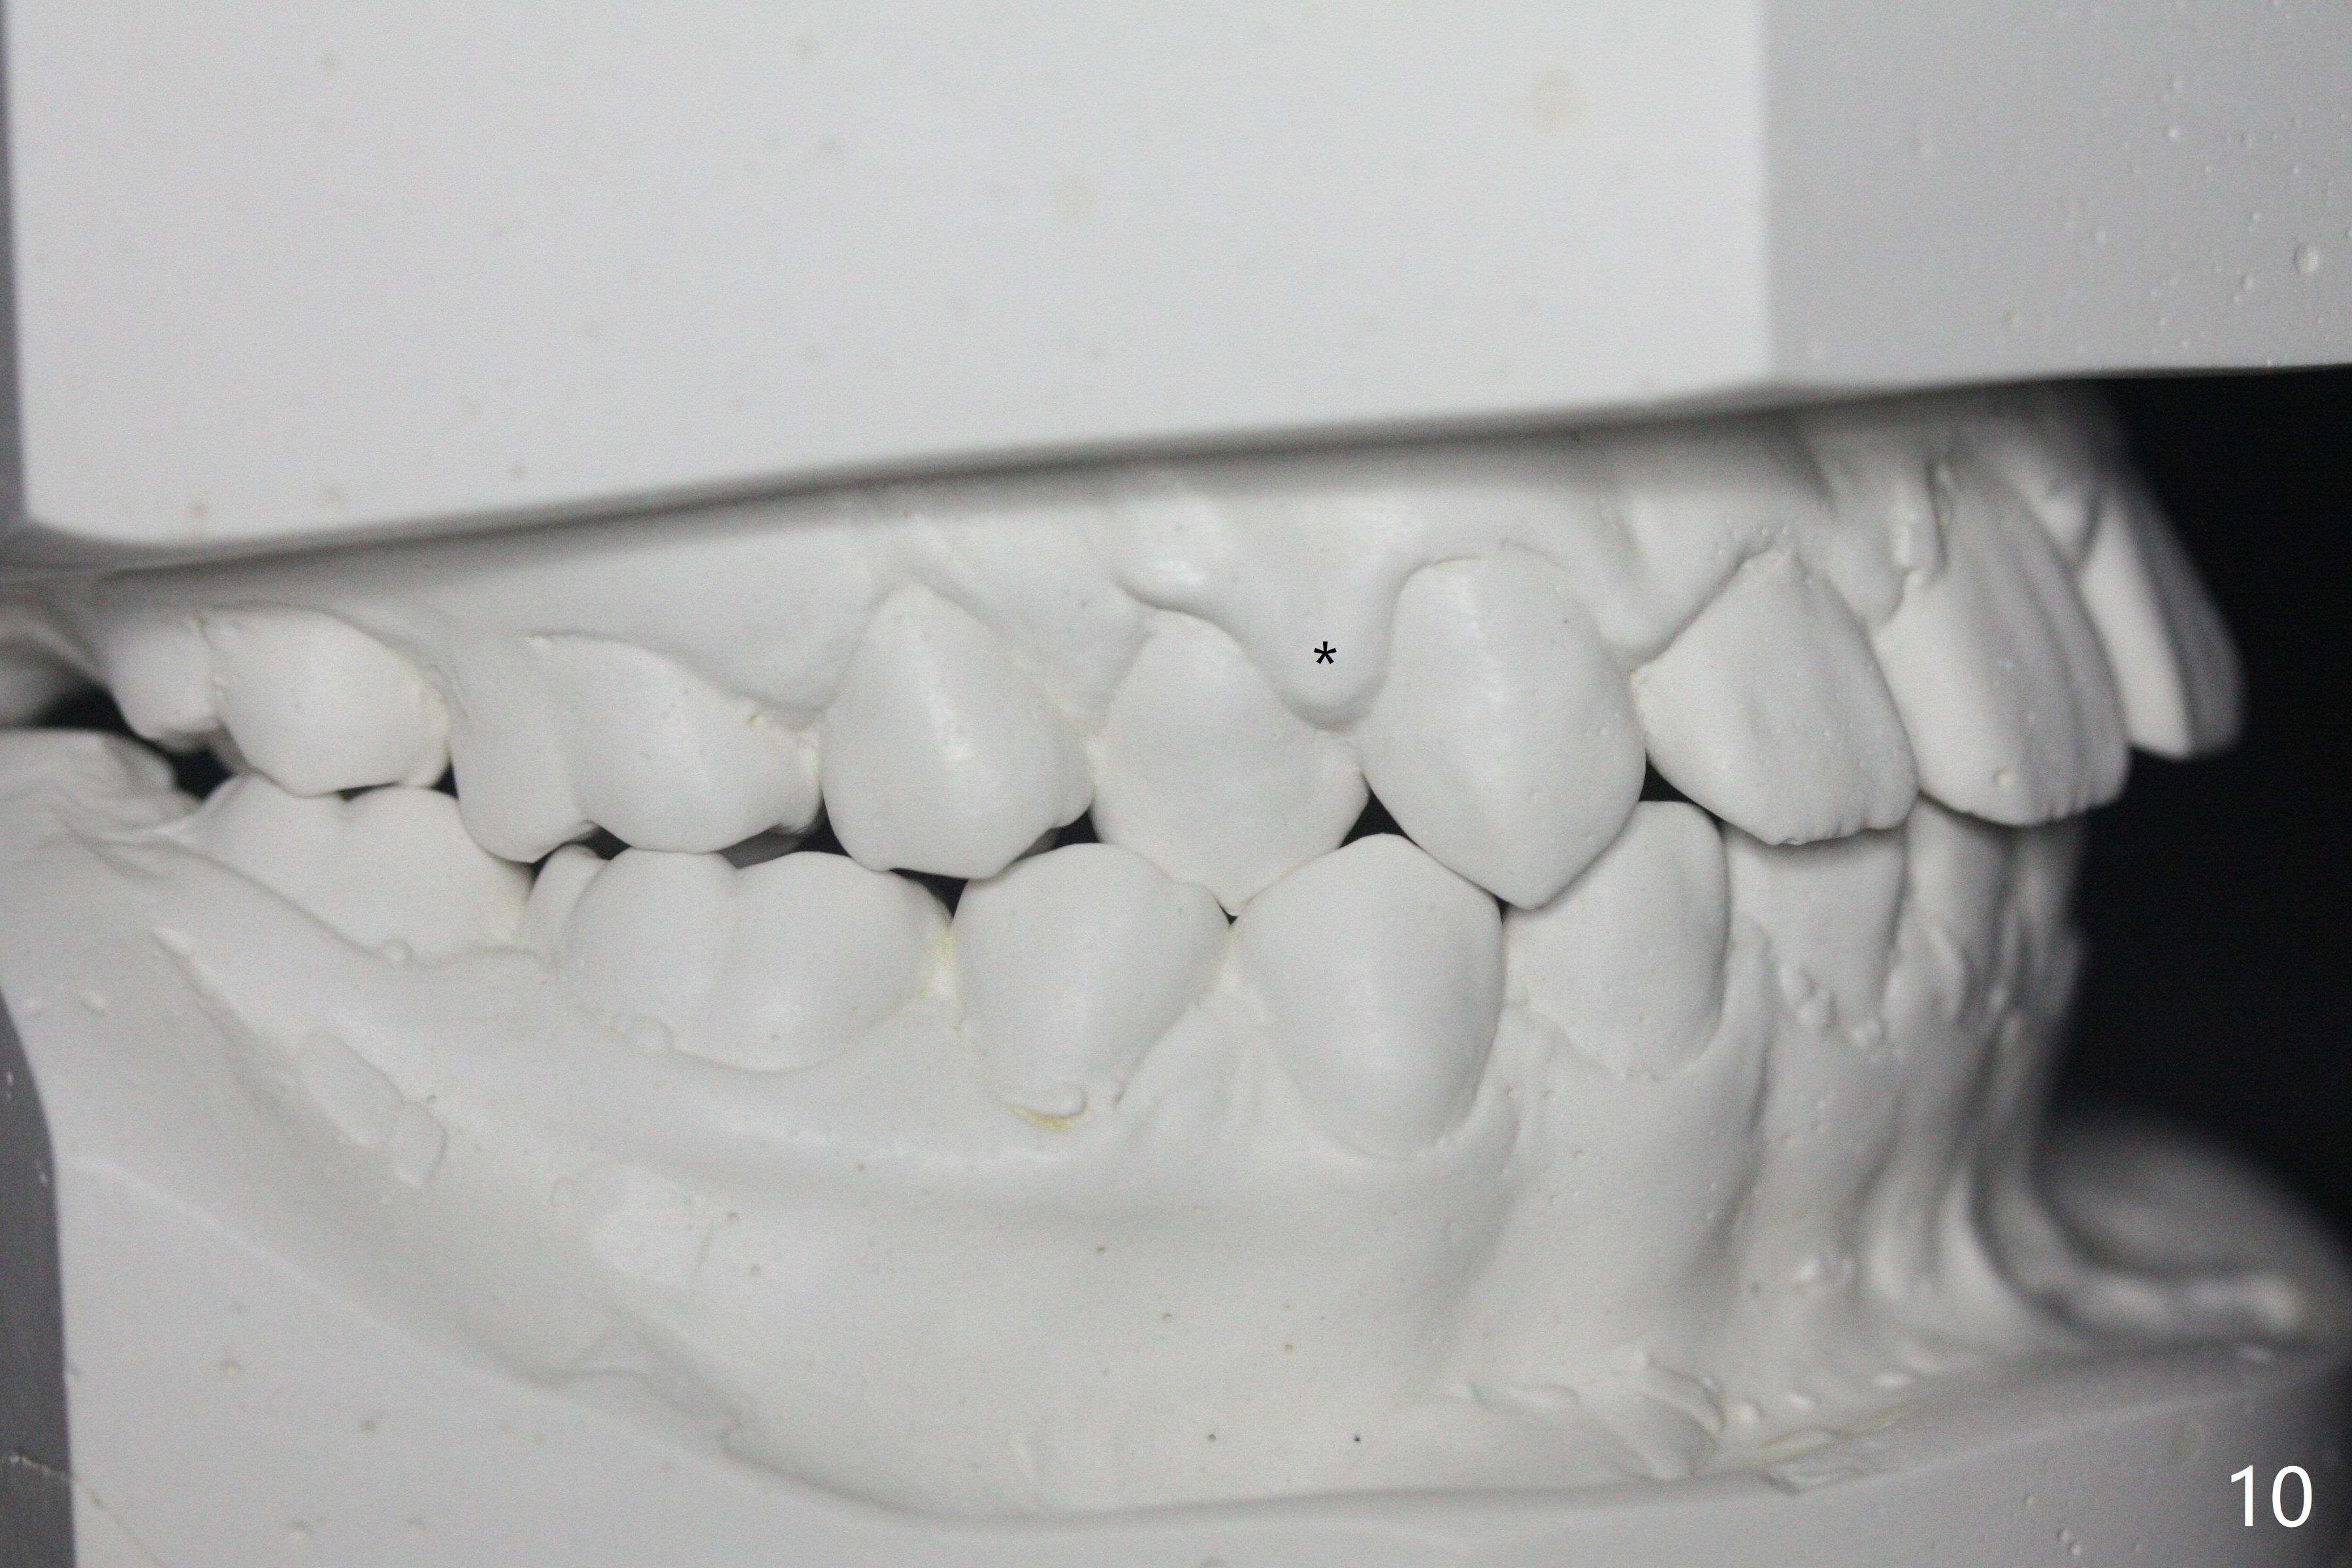

A 14-year-old woman, used to be a dental phobic (Fig.13), agrees with orthodontic treatment. Her mother is concerned about UL1 protrusion (Fig.8,11) and decalcification (Fig.8 *) and UR4 cross bite (Fig.7,10,14). There is mild lip constraint (Fig.1,3), as related to light dental protrusion (Fig.2,4), although the upper dental midline is not deviated (Fig.2). History shows that UR3 erupts before UR D is extracted, which is associated with UR4 cross bite. After arch expansion, consider proximal reduction to reduce anterior overjet if present. In fact that latter is not done; instead Class II is conducted.